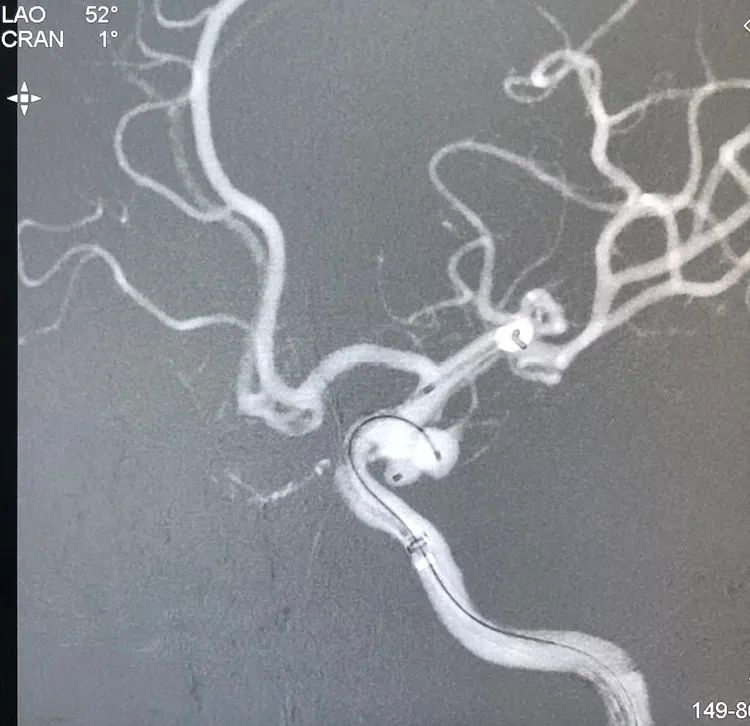

计划支架结合双微导管技术栓塞。6F Navien中间导管在6F长鞘支撑下抵达左颈内动脉破裂孔段。左颈内动脉工作位(LAO 52°)路图下,经Navien送入三套微导管,Headway-21支架导管进入左大脑中动脉;第一根Echelon-10微导管(甲管,头端塑成C形)在Synchro-14微导丝引导下进入大分叶;第二根Echelon-10微导管(乙管,头端塑成猪尾形)进入小分叶:

LVIS支架(3.5-15)辅助下双微管栓塞动脉瘤,先经甲管向大分叶内依次填入5枚弹簧圈(QC-6-15-3D,4-12-HELIX,3-8-HELIX,3-8-HELIX,2-8-HELIX),少量弹簧圈挤入小分叶;再经乙管向小分叶内依次送入3枚弹簧圈(APB-3-8-3D-ES,2-6-HX-ES,1.5-4-HX-ES);最后继续经乙管送入3枚弹簧圈(APB-1.5-3-HX-ES,1-3-HX-ES,1-3-HX-ES)封闭瘤颈: